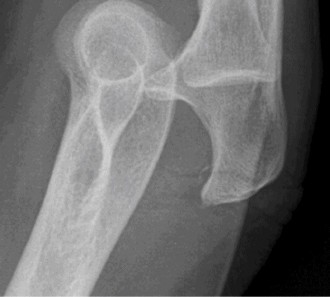

Treat a patient with infected total shoulder arthroplasty? CASE 21 A 70-year-old, right-hand-dominant female presents to clinic complaining of 4 years of gradually worsening chronic right shoulder pain and stiffness. She says the pain is worse at night and with any range of motion, denies a history of trauma, pain in other extremities, or numbness or tingling of the right upper extremity. She notes that her mother suffered from rheumatoid arthritis that affected her shoulder. Physical examination reveals decreased muscle bulk over the right supra- and infraspinatus fossae compared to the contralateral side, limited active and passive ROM, marked weakness with external rotation, and 4+/5 strength with shoulder abduction. X-rays of the right shoulder are shown in Figures 2–58 and 2–59.

Figure 2–58

Figure 2–59

The correct answer is (C). Rotator cuff tear arthropathy consists of a combination of rotator cuff insufficiency, glenohumeral joint degenerative changes, and superior humeral head migration. It is more common in women and also more often found on the dominant side. The patient’s clinical examination with weakened external

rotation and muscle atrophy signaling incompetent supra- and infraspinatus muscles point to rotator cuff insufficiency, and her plain films reveal narrowed glenohumeral joint space as well as superior migration of the humeral head. Choice D is incorrect because, while radiographs would show narrowing of the glenohumeral joint space, they would also likely show numerous osteophytes and posterior wear of the glenoid. Choice B is incorrect because, while adhesive capsulitis does present as decreased active and passive range of motion, the patient’s constellation of symptoms pointing towards rotator cuff insufficiency along with the radiographs make cuff tear arthropathy the more likely choice. Finally, Choice A is incorrect because even though she has a positive family history of rheumatoid arthritis, it is less likely to present only in a single joint. Also, rheumatoid arthritis on radiography appears more as an erosive process without the characteristic superior migration of the humeral head.

The correct answer is (A). Superior migration of the humeral head would be most indicative of chronic rotator cuff insufficiency associated with cuff tear arthropathy, as it is a direct result of the inability of the rotator cuff tendons to help maintain the humerus in its normal position. Acetabularization of the undersurface of the acromion is commonly associated with superior migration of the humeral head found in rotator cuff tear arthropathy, and can be assessed using the Hamada classification, which is based on measurements of the acromiohumeral interval on radiography (Table 2–8). Choices B and C are incorrect because, while narrowed glenohumeral joint space and subchondral sclerosis are associated with rotator cuff arthropathy on radiographs, they indicate degenerative joint changes rather than chronic rotator cuff insufficiency. Choice D is incorrect because it is not a specific sign of rotator cuff arthropathy.